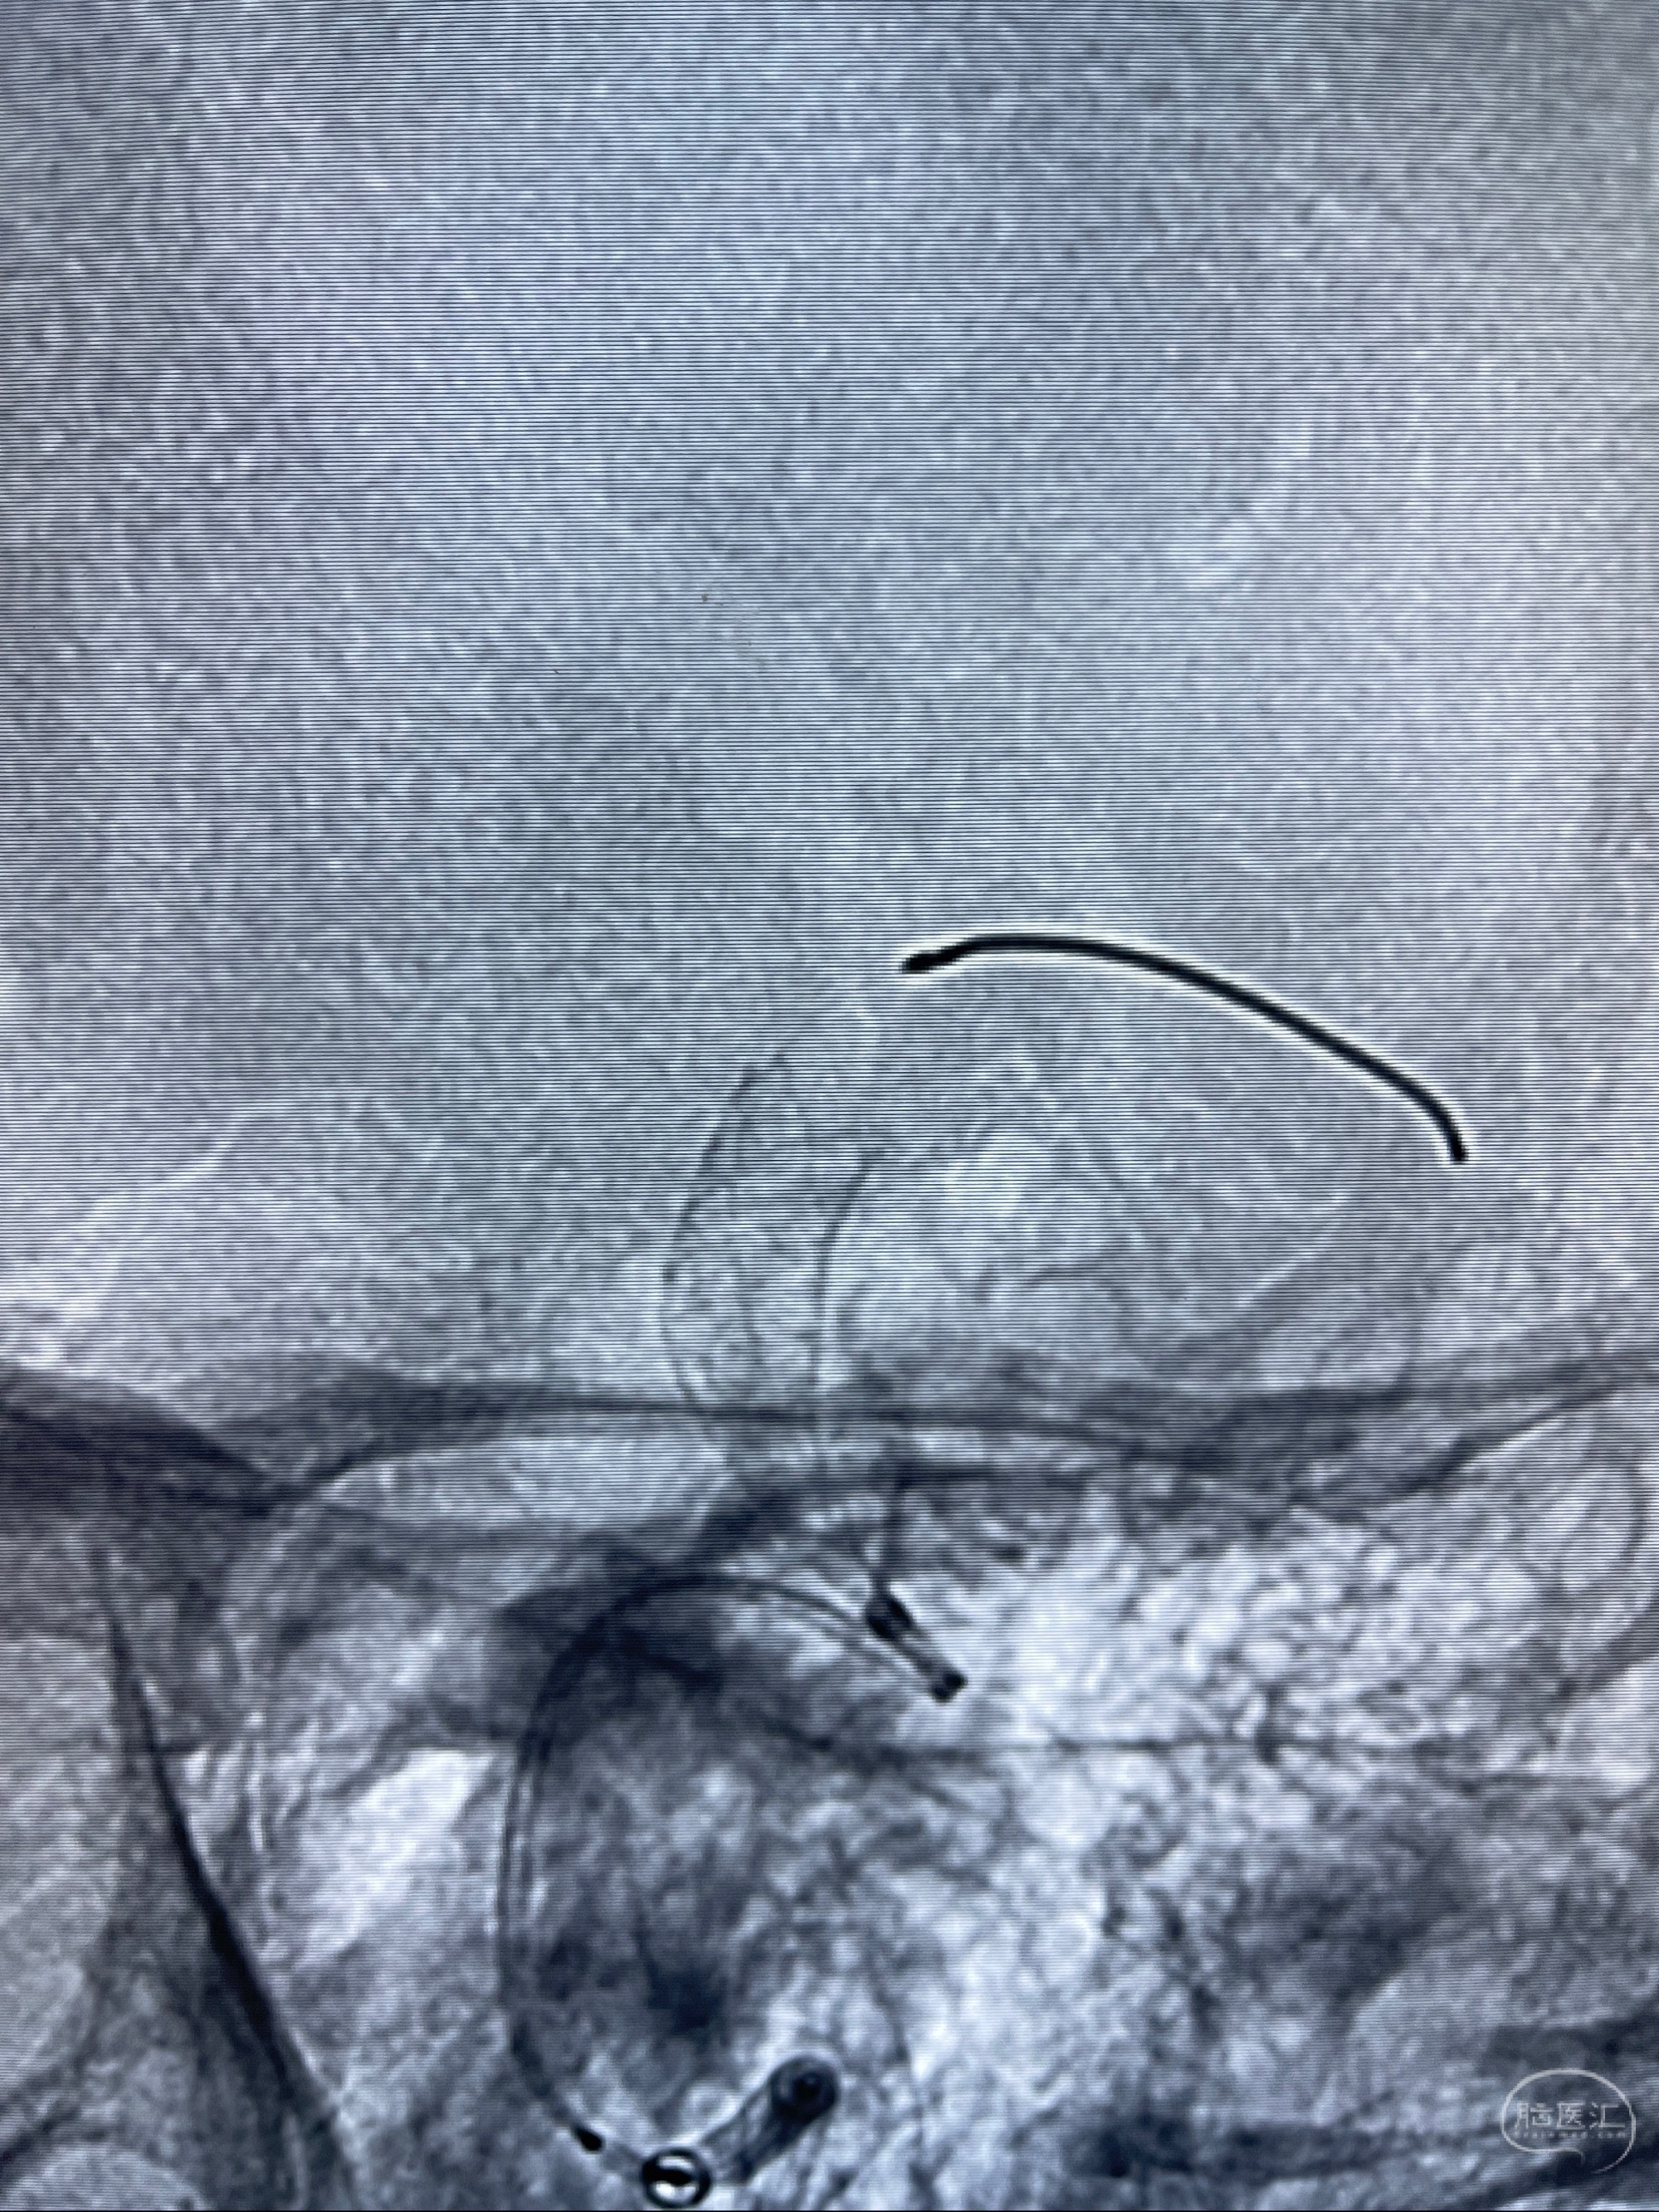

2023-07-27全脑血管造影:双侧颈内动脉眼动脉段动脉瘤,右侧较大

2023-08-01全麻下行双侧颈眼动脉瘤支架辅助栓塞

- pipeling4.5-20mm

- pipeline 4.0-20mm